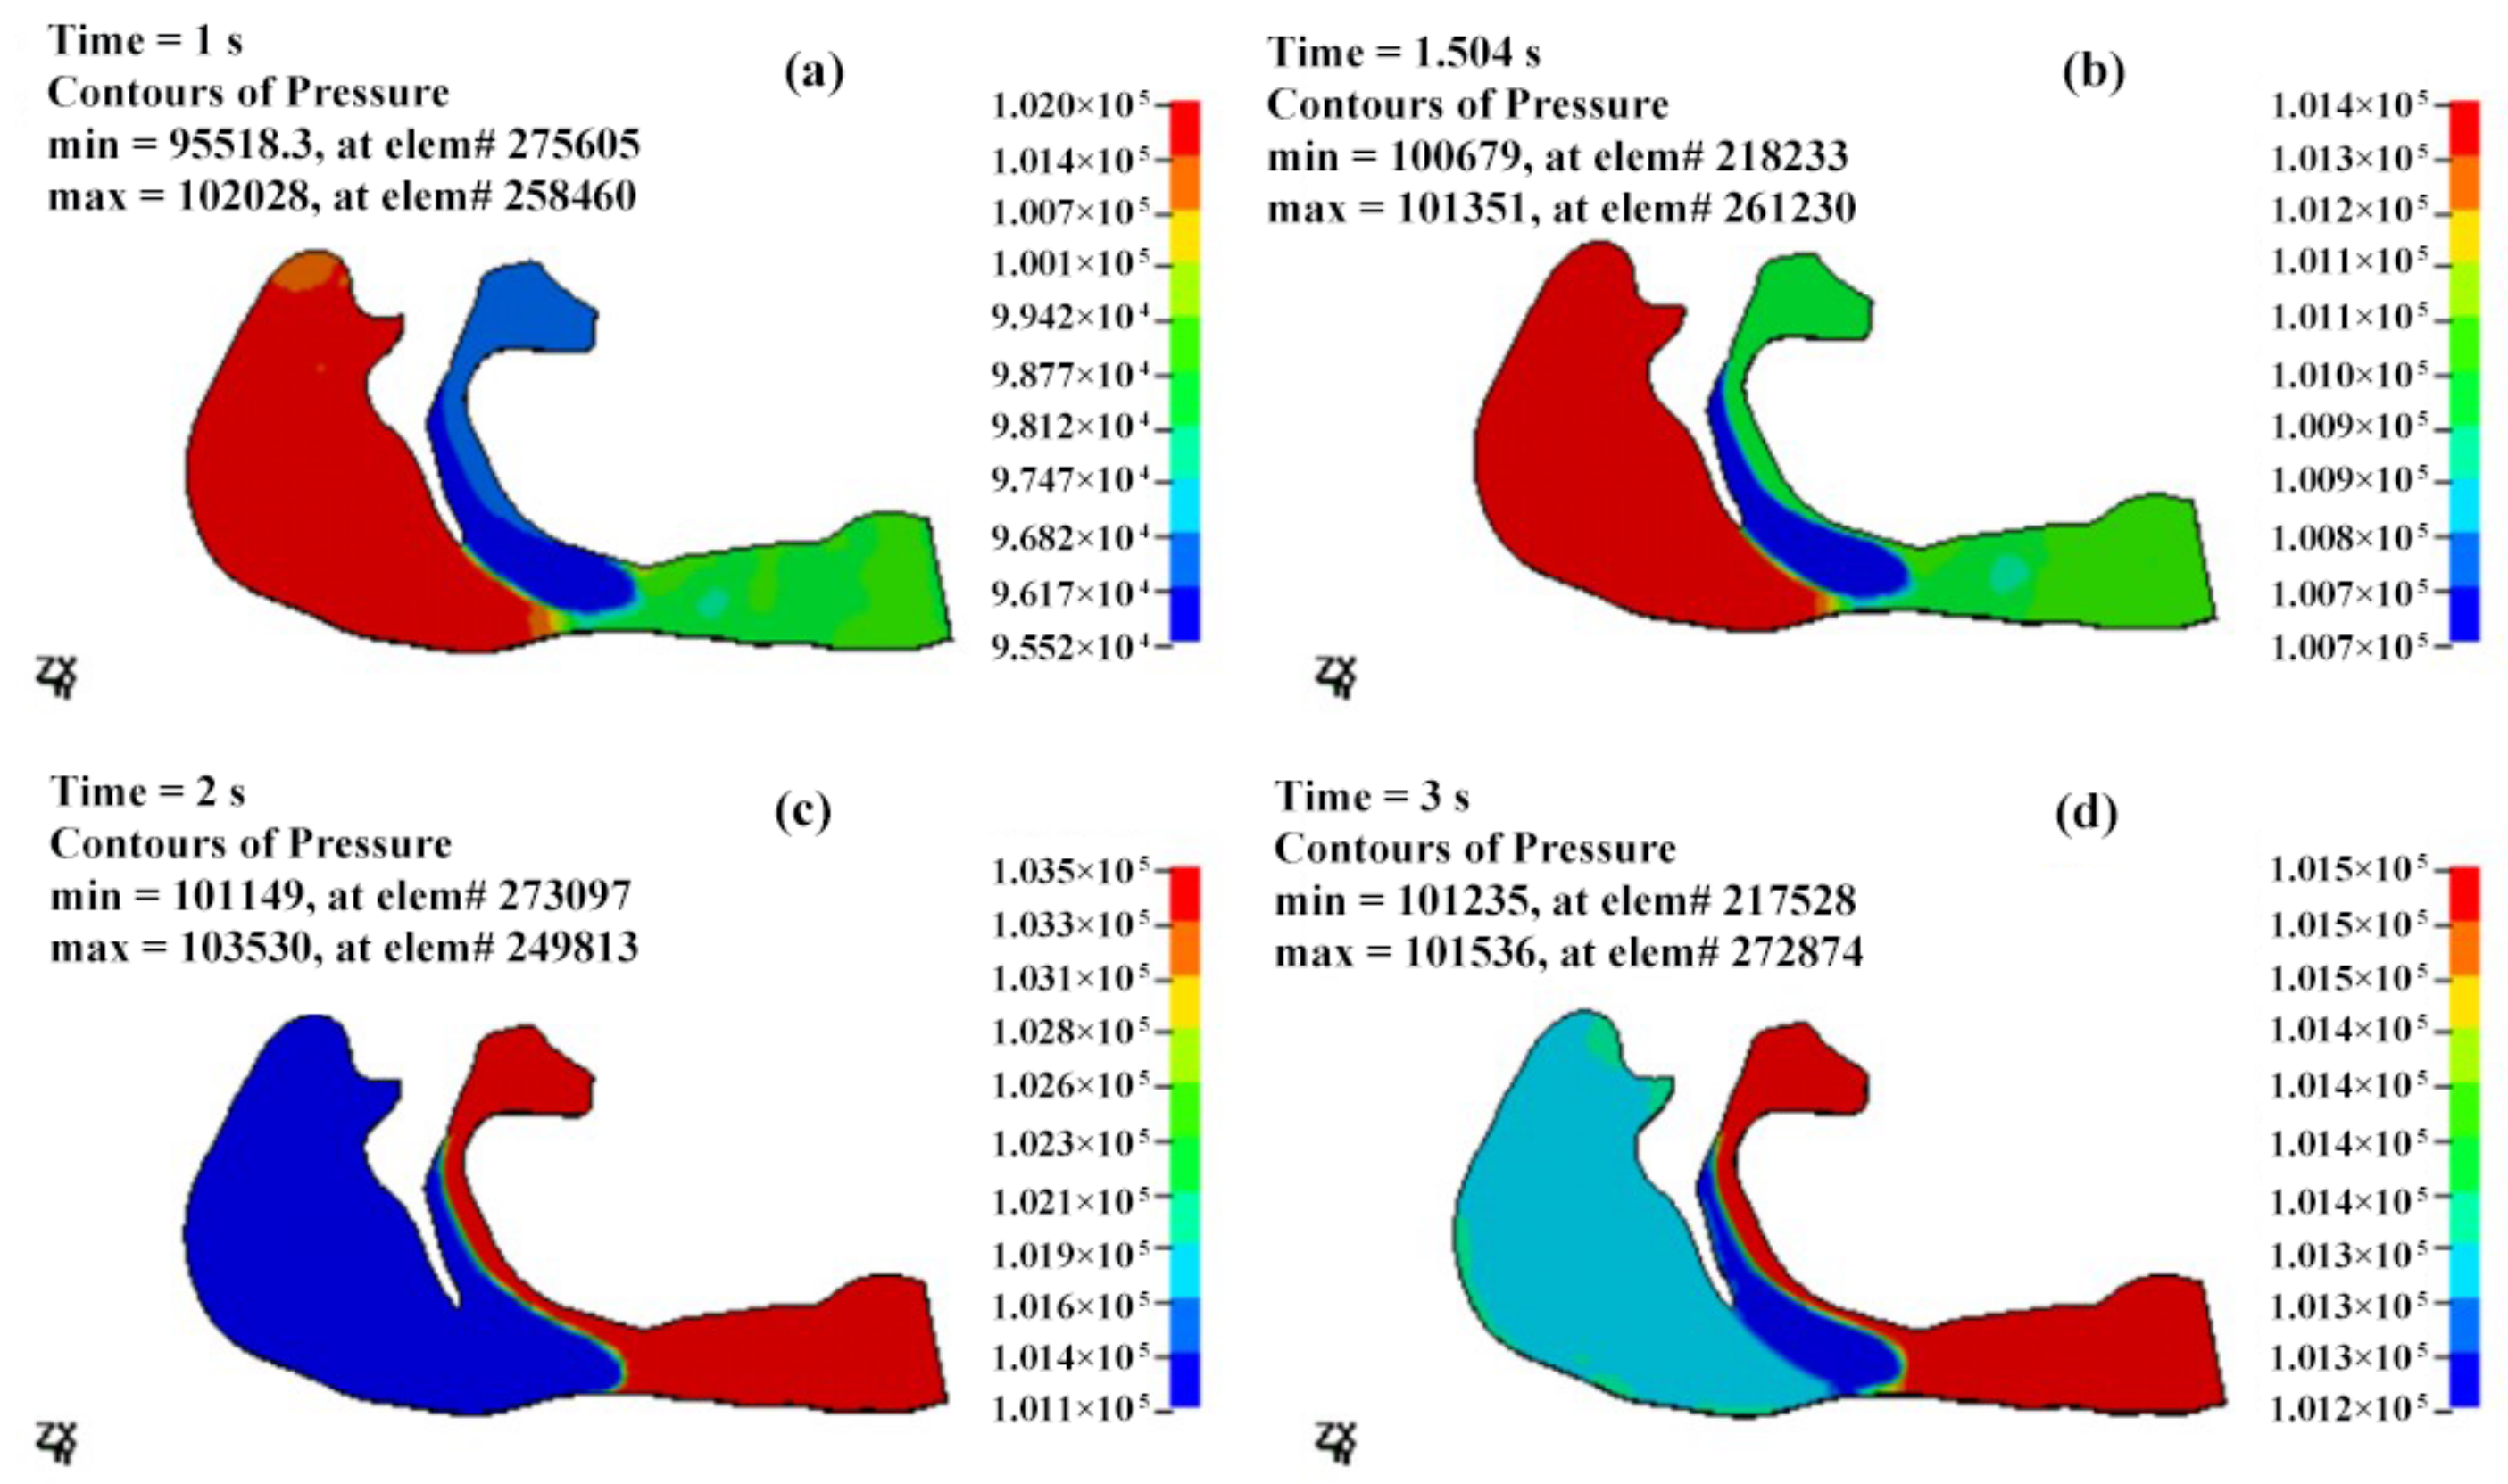

3.2.1. The Pressure Field of the Cavity

- The airflow characteristics during the inhalation phase are noticeably different from those in the exhalation phase for both eupnea and apnea. As the OSAHS patient breathes, the minimum pressure occurs alternately between the soft palate and the anteroposterior wall of pharynx, which causes the soft palate to vibrate during respiration, and therefore, the patient snores in sleep.

- The mechanical environment of the airway is directly dependent on the action of the airflow. If the mechanical properties of the soft palate remain unchanged, the pressure makes the soft palate collapse in apnea. In eupnea, the pressure allows the airflow to pass freely through the airway.

| T (s) | Pmax (Pa) | Pmin (Pa) | ΔP (Pa) | Pressure Drop (Pa) |

|---|---|---|---|---|

| 0.5 | 101,408 | 98,943 | 2465 | −1301 |

| 1 | 102,028 | 95,518 | 6510 | −2495 |

| 1.25 | 101,306 | 98,671 | 2635 | −1712 |

| 1.5 | 101,351 | 100,679 | 672 | −321 |

| 1.75 | 102,387 | 101,189 | 1198 | 1010 |

| 2 | 103,530 | 101,149 | 2381 | 2099 |

| 2.5 | 103,034 | 101,184 | 1850 | 1591 |